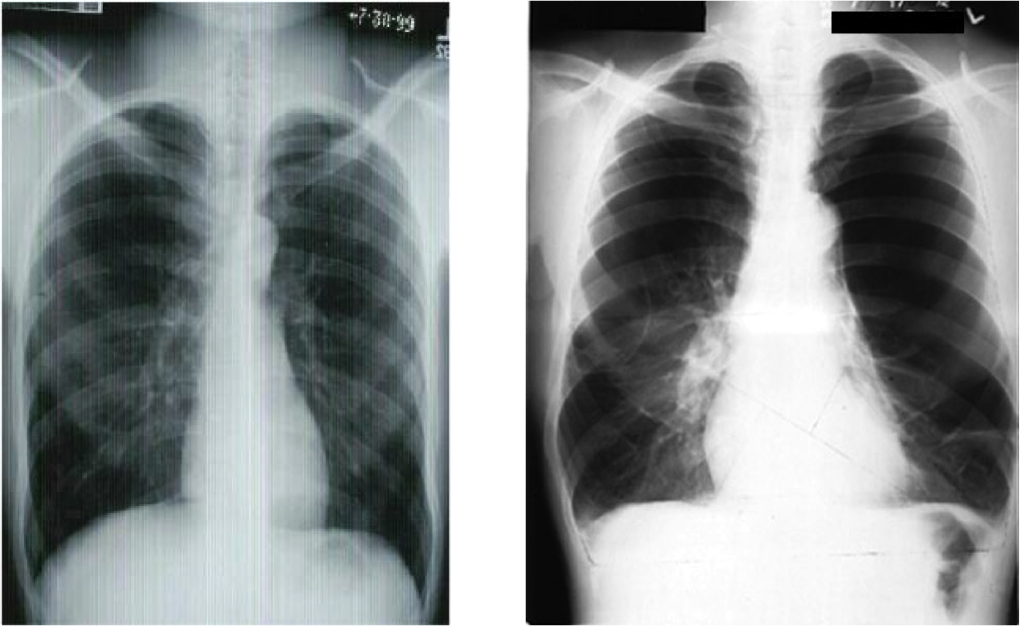

Which image is of a patient with emphysema?

Discuss the findings of the X-Ray of the patient with emphysema.

The image on the right is the emphysema patient.

Hyperinflation of the lungs (black is air), flattened out diaphragm.